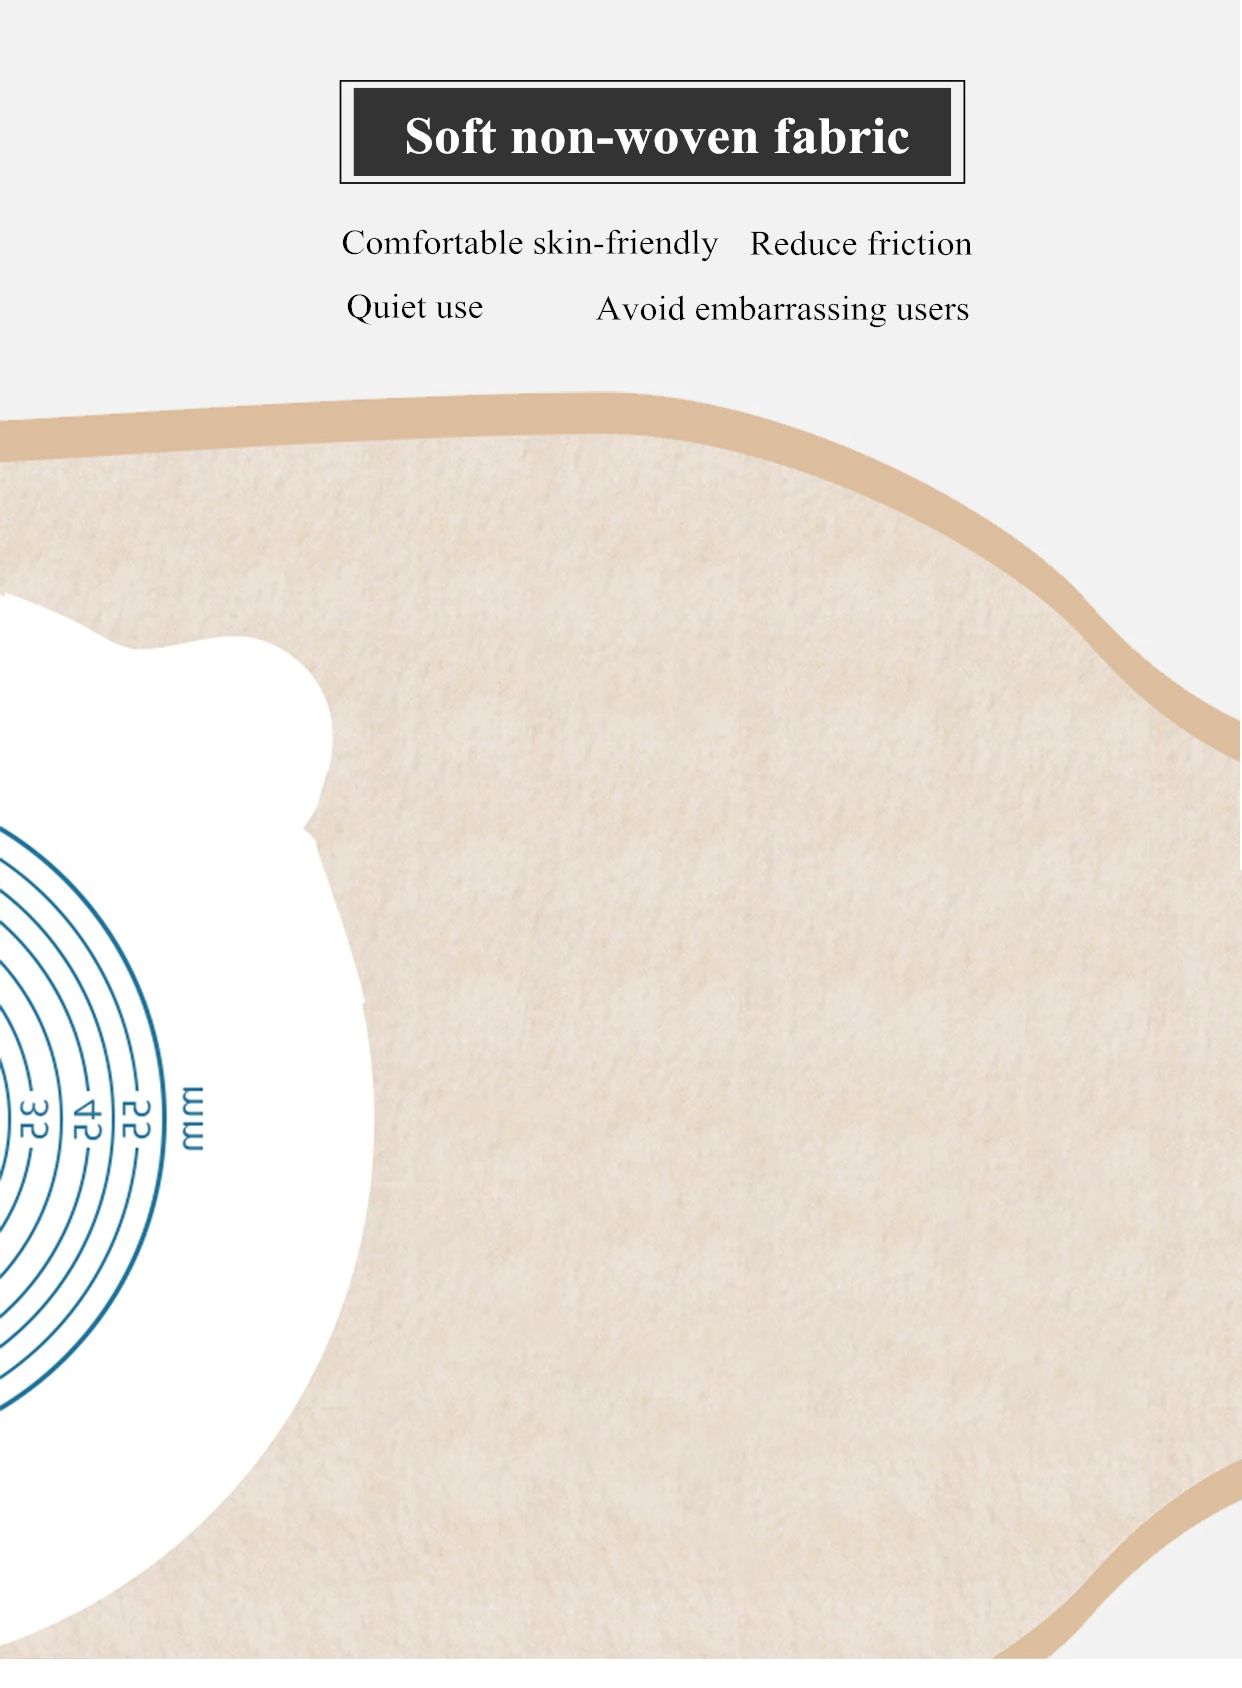

Material: No tejido

Descripción del producto La bolsa de cuidado de ostomía combina la barrera de la piel y la bolsa de colección en un sistema simple y fácil de administrar, proporcionando una gran simplicidad. La bolsa de colostomía es fácil de aplicar con el cierre de Velcro adjunto, proporcionando seguridad, ya que los sujetadores de plástico se bloquean en su lugar, fáciles de vaciar y irrigar. El propósito de reemplazar la ostomía 1. Observa la mucosa del estoma, las suturas circundantes y la piel circundante. 2. Limpia la piel alrededor del estoma, reduce el olor y aumenta la comodidad. 3. Evita que el agua fecal contamine la incisión abdominal a través de la fuga del chasis. 4. Si hay impregnación, asegúrese de reemplazarla a tiempo. Se recomienda cambiar el tiempo de 3-5 días para garantizar una respiración efectiva de la piel. Sentido común de la vida ostomía 1. Comer uniformemente, beber mucha agua y comer más verduras y frutas. 2. Evite comer demasiado rápido y tragar aire, masticar alimentos lentamente, Evite hablar mientras come, evite comer demasiado de una vez. 3. Evite las comidas con alto contenido de fibra y evite el bloqueo del estoma. 4. La ropa es suave y cómoda. 5. Evita el trabajo para aumentar la presión abdominal (como extraer objetos pesados). 6. Mantenga su estado de ánimo feliz. Paquete 10 unids/caja bolsa de ostomía